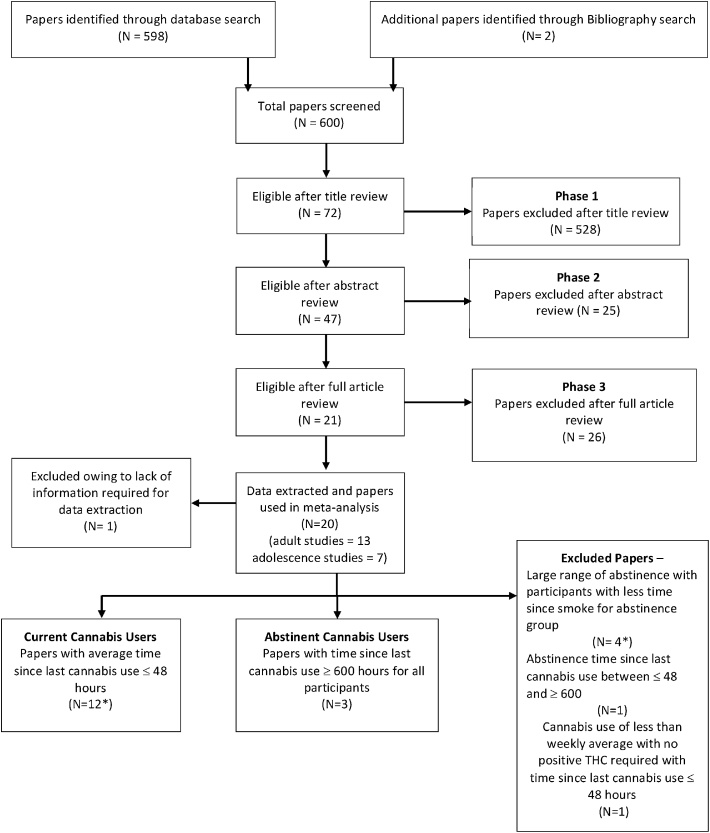

A systematic search was competed on the 13/12/2017 following the Cochrane Handbook (ref. JPT, 2011) and the MOOSE (ref. Stroup et al., 2000) guidelines, using the database PubMed. Two categories of search terms were used: 1) cannabis, marijuana, marihuana, THC, tetrahydrocannabinol and 2) imaging, fMRI, functional activation, BOLD. Following screening through abstract to meet inclusion criteria.

Manuscripts were separated into three categories, based on the type of cannabis-using groups reported. Those that reported at least one comparison with current cannabis users (CCU) or with abstinent cannabis users (ACU) were included while those that did not report either of the previous comparisons were excluded (flow-chart in Fig. 1; number of manuscripts indicated by ‘N’). CCU were identified as those in whom the time interval between the last cannabis smoke and scanning was a maximum of 48 h (so as to avoid peak withdrawal symptoms (ref. Budney et al., 2004)) with inclusion criteria requiring at least an average weekly use of cannabis or a positive test for THC or its metabolites at urine drug screening. ACU were required to have a monitored period of abstinence from cannabis use for at least 600 h/25 days based on previous evidence of upper limit of period of detection of THC metabolites in urine (ref. Schreiner and Dunn, 2012b) and to have provided a negative urine test for THC.

Twenty studies were identified as meeting study inclusion criteria as detailed earlier. Of those, twelve manuscripts met inclusion criteria as reporting CCU, with 22 separate comparisons, comparing 361 CCU to 394 NU (Table 1). Three manuscripts were identified as having studied ACU with 5 separate comparisons, comparing 98 ACU to 106 NU (Table 1). Five manuscripts and one comparison from another manuscript were excluded as they had large ranges of abstinence within their cannabis using group (ref. Chang et al., 2006; ref. Heitzeg et al., 2015; ref. Jager et al., 2013; ref. Nestor et al., 2010, ref. 2008; ref. van Hell et al., 2010) or had abstinent periods (between 48 and 600 h) that were not consistent with our pre-defined abstinence criteria for inclusion in the ‘abstinent users’ group. Number of studies included for each comparison are indicated by ‘k’ and number of participants for each comparison are indicated by ‘n’ henceforth in the text as well as in the relevant sections of tables or figures.

All studies qualifying for the ACU group, were carried out in adolescent users. Further meta-analysis comparing ACU and CCU, using only adolescent studies was completed. Data from three manuscripts reporting on current adolescent users, with four separate comparisons, with 69 CCU and 70 NU were used for comparison with the abstinent adolescent user group described above. Results for all meta-analyses are reported in Table 3 and Fig. 2.